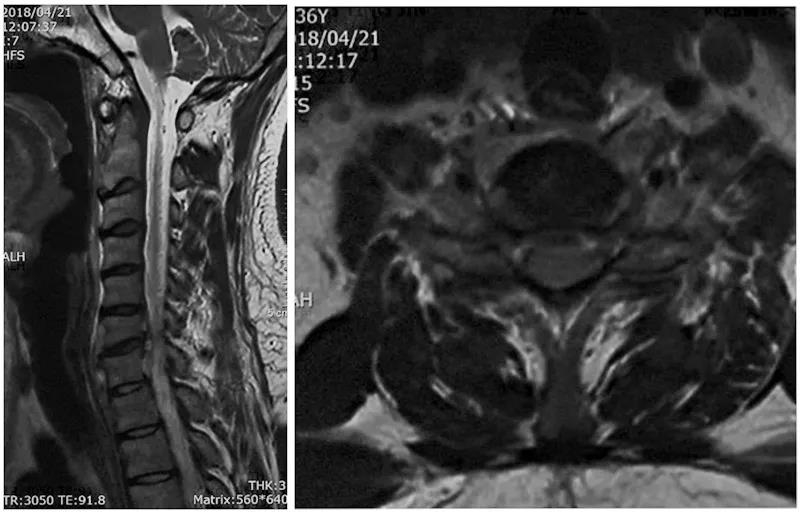

术前X线

术前CT

术前核磁